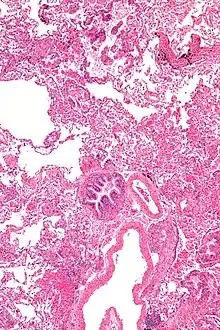

Grossly, LAM lungs are enlarged and diffusely cystic, with dilated air spaces as large as several centimeters in diameter.[106][107] Microscopic examination of the lung reveals foci of smooth muscle-like cell infiltration of the lung parenchyma, airways, lymphatics, and blood vessels associated with areas of thin-walled cystic change. LAM lesions often contain an abundance of lymphatic channels, forming an anastomosing meshwork of slit-like spaces lined by endothelial cells. LAM cells generally expand interstitial spaces without violating tissue planes but have been observed to invade the airways, the pulmonary artery, the diaphragm, aorta, and retroperitoneal fat, to destroy bronchial cartilage and arteriolar walls, and to occlude the lumen of pulmonary arterioles.[106]

There are two major cell morphologies in the LAM lesion: small spindle-shaped cells and cuboidal epithelioid cells.[108] LAM cells stain positively for smooth muscle actin, vimentin, desmin, and, often, estrogen and progesterone receptors. The cuboidal cells within LAM lesions also react with a monoclonal antibody called HMB-45, developed against the premelanosomal protein gp100, an enzyme in the melanogenesis pathway.[108] This immunohistochemical marker is very useful diagnostically, because other smooth muscle-predominant lesions in the lung do not react with the antibody.[109] The spindle-shaped cells of the LAM lesion are more frequently proliferating cell nuclear antigen positive than the cuboidal cells, consistent with a proliferative phenotype.[108] Compared with cigar-shaped normal smooth muscle cells, spindle-shaped LAM cells contain less abundant cytoplasm and are less eosinophilic. Estrogen and progesterone receptors are also present in LAM lesions,[110][111][112] but not in adjacent normal lung tissue.[113] LAM lesions express lymphatic markers LYVE-1, PROX1, podoplanin and VEGFR-3. The smooth muscle-like cells of AMLs are morphologically and immunohistochemically similar to LAM cells, including reactivity with antibodies directed against actin, desmin, vimentin, and HMB-45 as well as estrogen and progesterone receptors.[114][115] Unlike the dilated airspaces in emphysema, the cystic spaces found in LAM may be partially lined with hyperplastic type II cells.[116]

Micrograph of lymphangioleiomyomatosis.